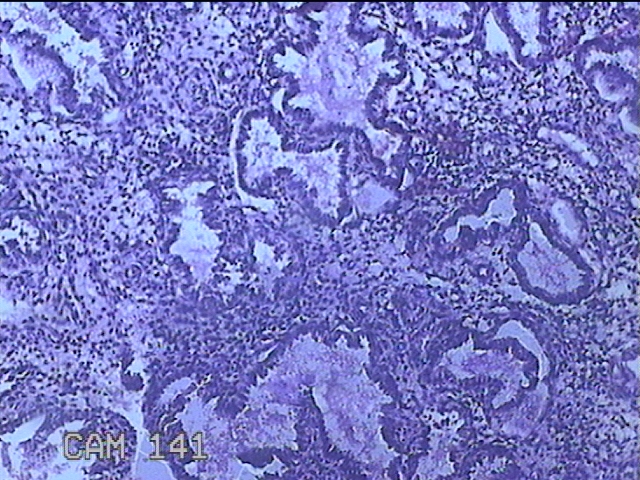

性别

女

年龄

41岁

临床诊断

异常子宫出血;取出子宫内节育器;子宫内膜炎

一般病史

阴道不规则流血2个月。

标本名称

宫腔内容物

大体所见

灰白暗红色不规则碎组织3.5x2.5x0.8cm一堆。